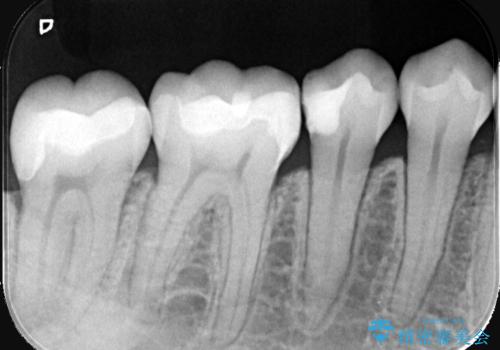

- 右下6番の奥歯に入っている金属の詰め物(メタルインレー)を気にされてご来院されました。お口の中の金属をなくしたいという患者様のご希望と、見た目の改善を目指し、天然歯に近い色と質感を持つセラミックインレーに交換する治療計画を立案しました。これにより、審美性の向上と、金属アレルギーのリスクがないメタルフリーの環境を実現することを目指しました。

治療では、まず古い金属のインレーを慎重に取り外し、内部に虫歯の再発がないかを丁寧に確認しました。歯を最小限だけ形成した後、精密な型取りから患者様の歯の色に合わせたオーダーメイドのセラミックインレーを作製しました。セラミックは、歯質との適合性が高く、プラークが付着しにくいため、虫歯の再発リスクを抑えるメリットもあります。適合性の高いセラミックインレーを装着することで、長年のコンプレックスだった銀歯がなくなり、機能的にも安定した自然な奥歯を取り戻していただけました。